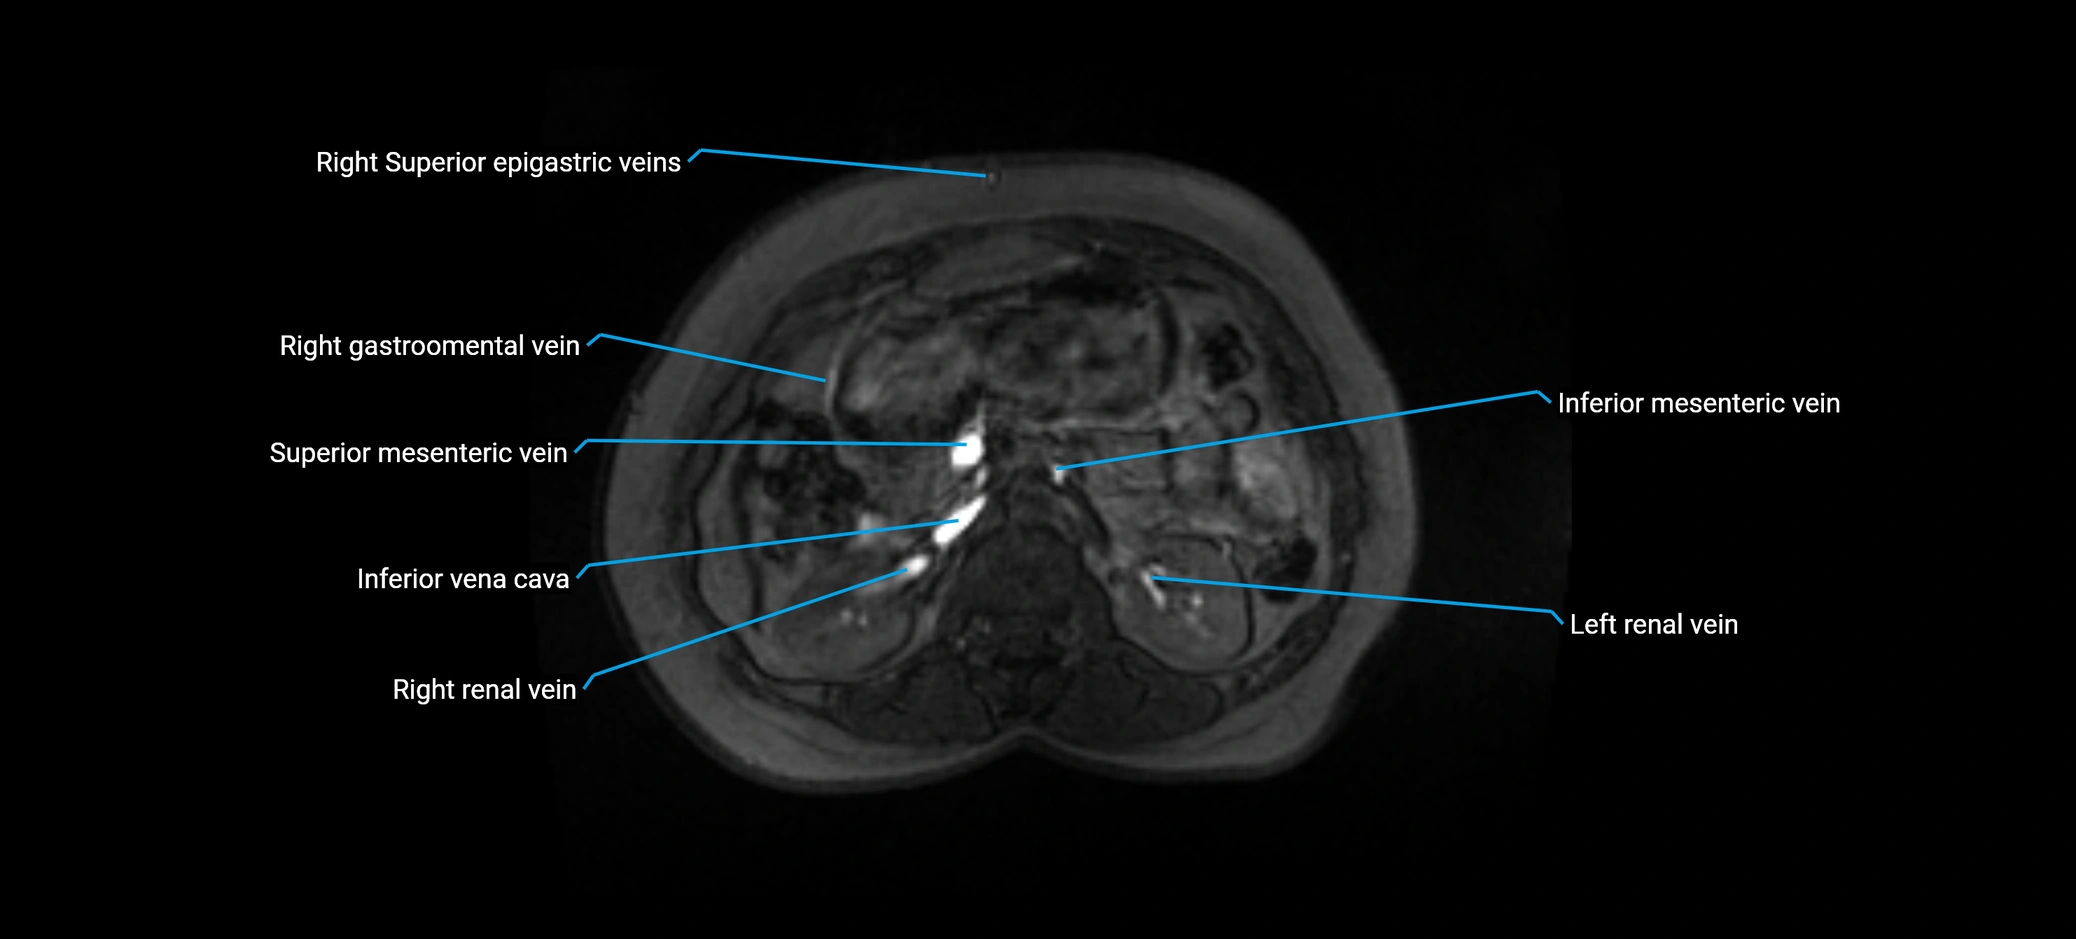

MRI image

image